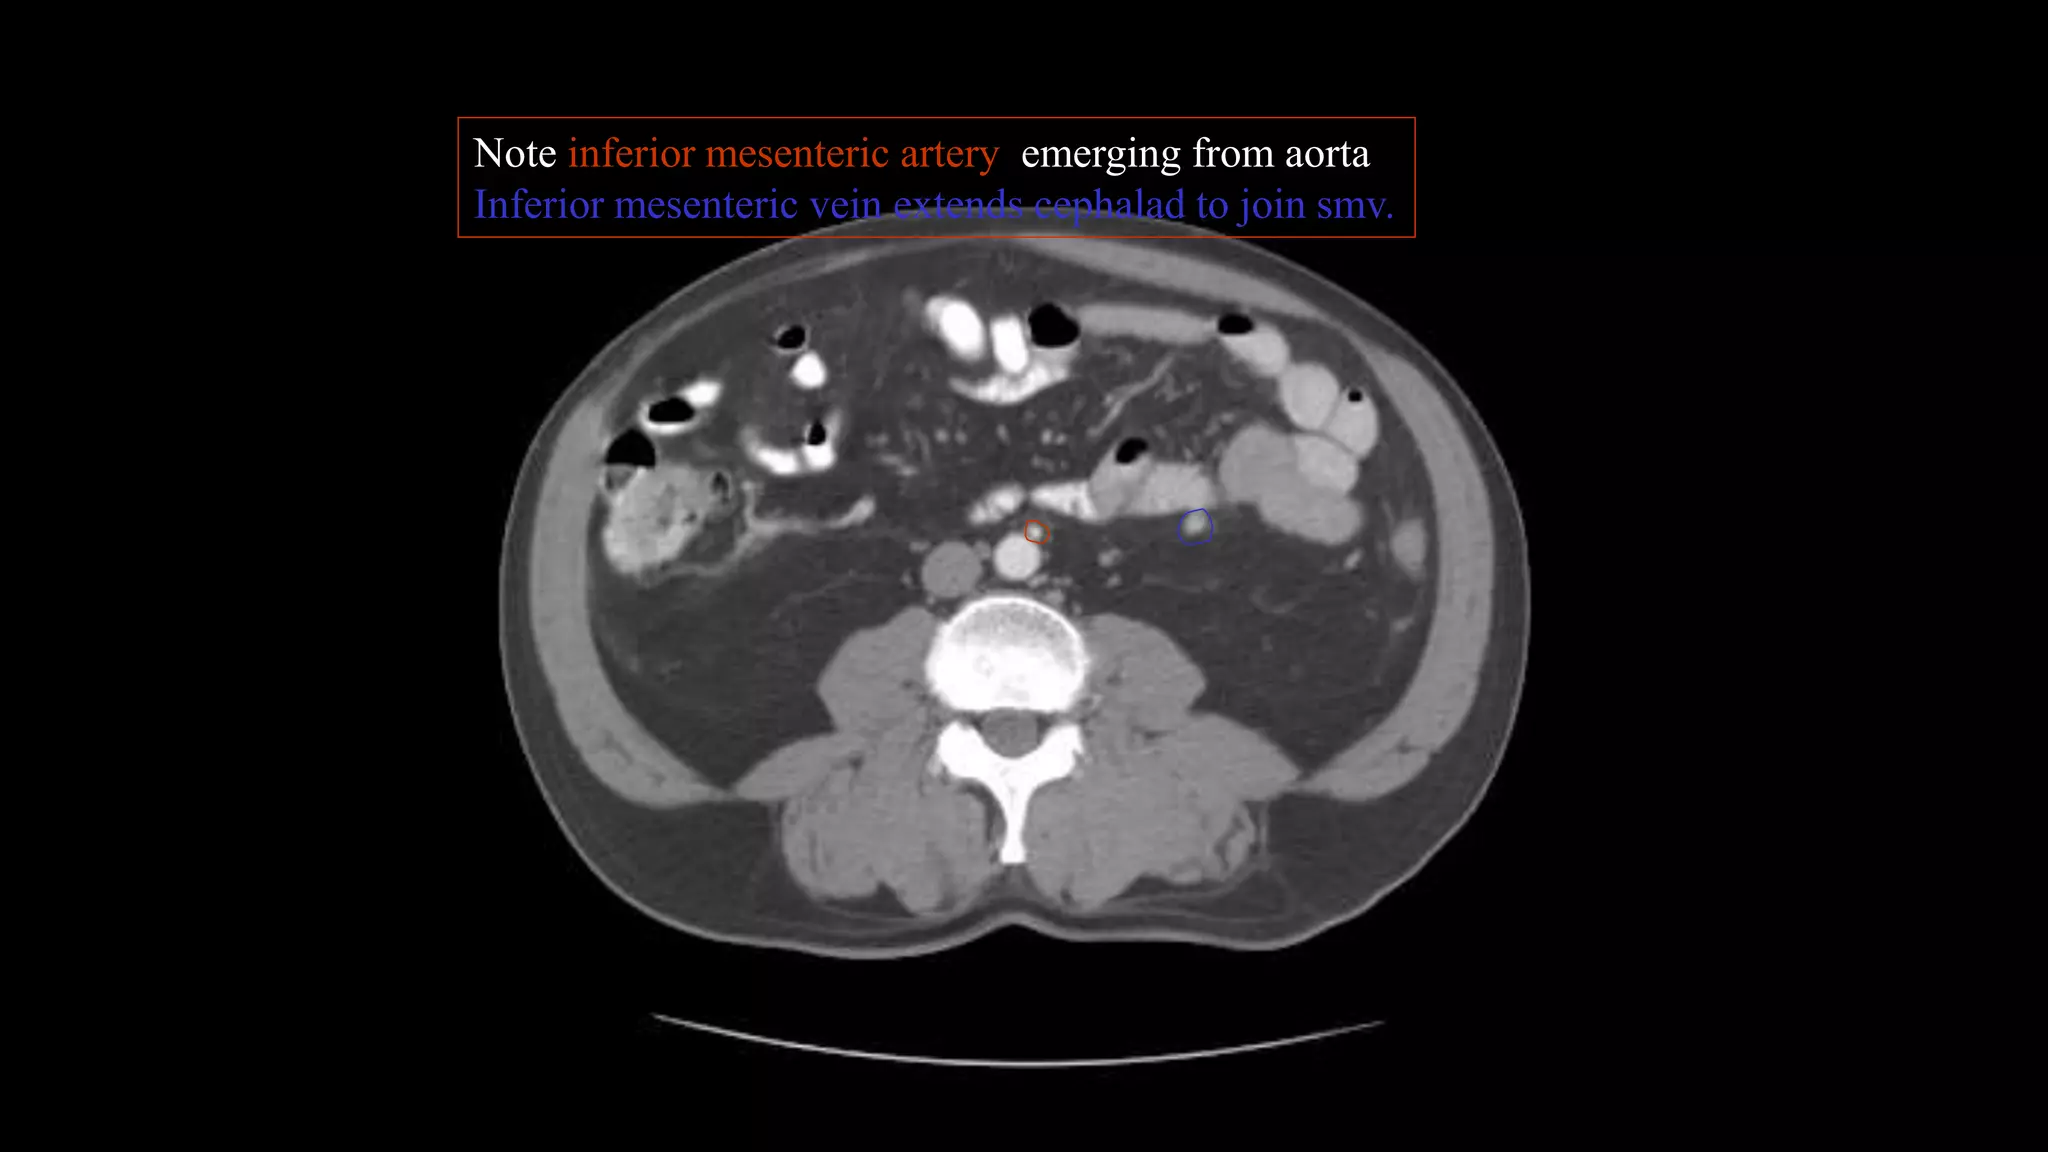

Note inferior mesenteric artery emerging from aorta

Inferior mesenteric vein extends cephalad to join smv.

Note inferior mesentericartery emerging from aorta Inferior mesenteric vein extends cephalad to join smv.